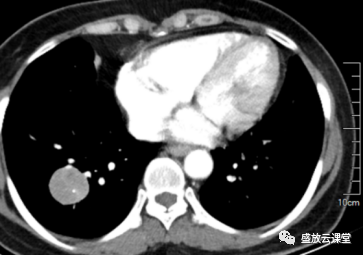

增强CT影像表现

右肺下叶基底段类圆形高密度影,大小约3.0cm×2.9cm

边缘规整,其内见点状钙化,增强扫描明显均匀强化

密度:密度较均匀,其内见点状钙化

强化方式:均匀强化

影像学特点(CT):右肺下叶基底段类圆形高密度影,边缘规整,密度较均匀,其内见点状钙化,增强扫描明显均匀强化